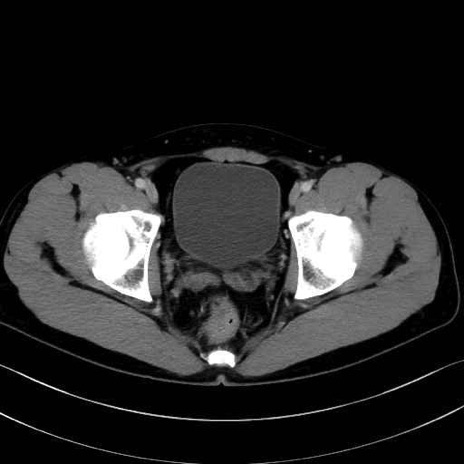

内閉鎖筋 (Obturator internus)

外閉鎖筋 (Obturator externus)

大腿方形筋 (Quadratus femoris)